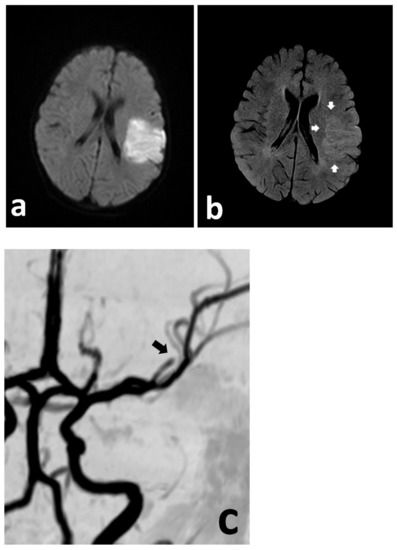

A previously healthy 3-year-old boy was admitted to the University of Missouri Columbia Children’s Hospital on 16 December 2020, with a 4-day history of acute gastrointestinal symptoms (i.e., nausea, vomiting, abdominal pain), fever, rash, shock, mild left ventricular myocardial dysfunction, elevated inflammatory markers (C-reactive protein, procalcitonin, ferritin, transaminases, interleukin-1, interleukin-6), and evidence of COVID-19 (RT-PCR, antigen test, serology positive) (Table 1), thereby satisfying the criteria of MIS-C [1,3,4,5,6]. He was rapidly treated with intravenous methylprednisolone (2 mg/kg/day, divided every 6 h), intravenous immunoglobulin (2 g/kg), enteral aspirin (81 mg per day), and prophylactic subcutaneous low-molecular-weight heparinoid (0.5 mg/kg twice daily). On the second inpatient day, he developed sudden weakness in the right arm and leg, aphasia, and an overall neurologic deficit that amounted to a Pediatric National Institutes Stroke Scale (PedNIHSS) score of 26. Magnetic resonance imaging (MRI) showed evidence of restricted diffusion consistent with ischemia of the territory of the middle division of the left middle cerebral artery—LMCA (md)—(Figure 1a), and yet, minimally increased signal of the analogous volume of tissue in the Flow Attenuation Inversion Recovery (FLAIR) sequence (Figure 1b). In addition, magnetic resonance angiography (MRA) demonstrated occlusion of the LMCA (md) (Figure 1c), leading to the decision to proceed with urgent thrombectomy. Cerebral angiography confirmed the expected occluded artery (Figure 2a), which was successfully recanalized by retriever thrombectomy (Figure 2b,c). Successful reperfusion [Thrombolysis in Cerebral Infarction (TICI) = 2b] of the affected vascular territory was immediately confirmed via digital parenchymography (Figure 3). Over the 12–24 h following the procedure, the child regained spontaneous movement of his right arm and leg and began to communicate verbally (PedNIHSS = 10). He continued to progressively improve, reaching near-normal motor and language function (PedNIHSS = 5) at hospital discharge one week later, and displayed no neurologic deficits at 30 days in the outpatient clinic. Additional imaging studies, including echocardiography and venous Doppler ultrasound of all limbs, proved unremarkable. However, he was found to be heterozygous for Factor V Leiden mutation.

Figure 1. Urgent MRI study demonstrating focally restricted diffusion in the MCA (md) territory (a), with only discrete hyperintensity in the FLAIR sequence (b) (white arrows), indicating at least a partial mismatch. The MRA demonstrates cut-off of the MCA (md) (c) (black arrow).